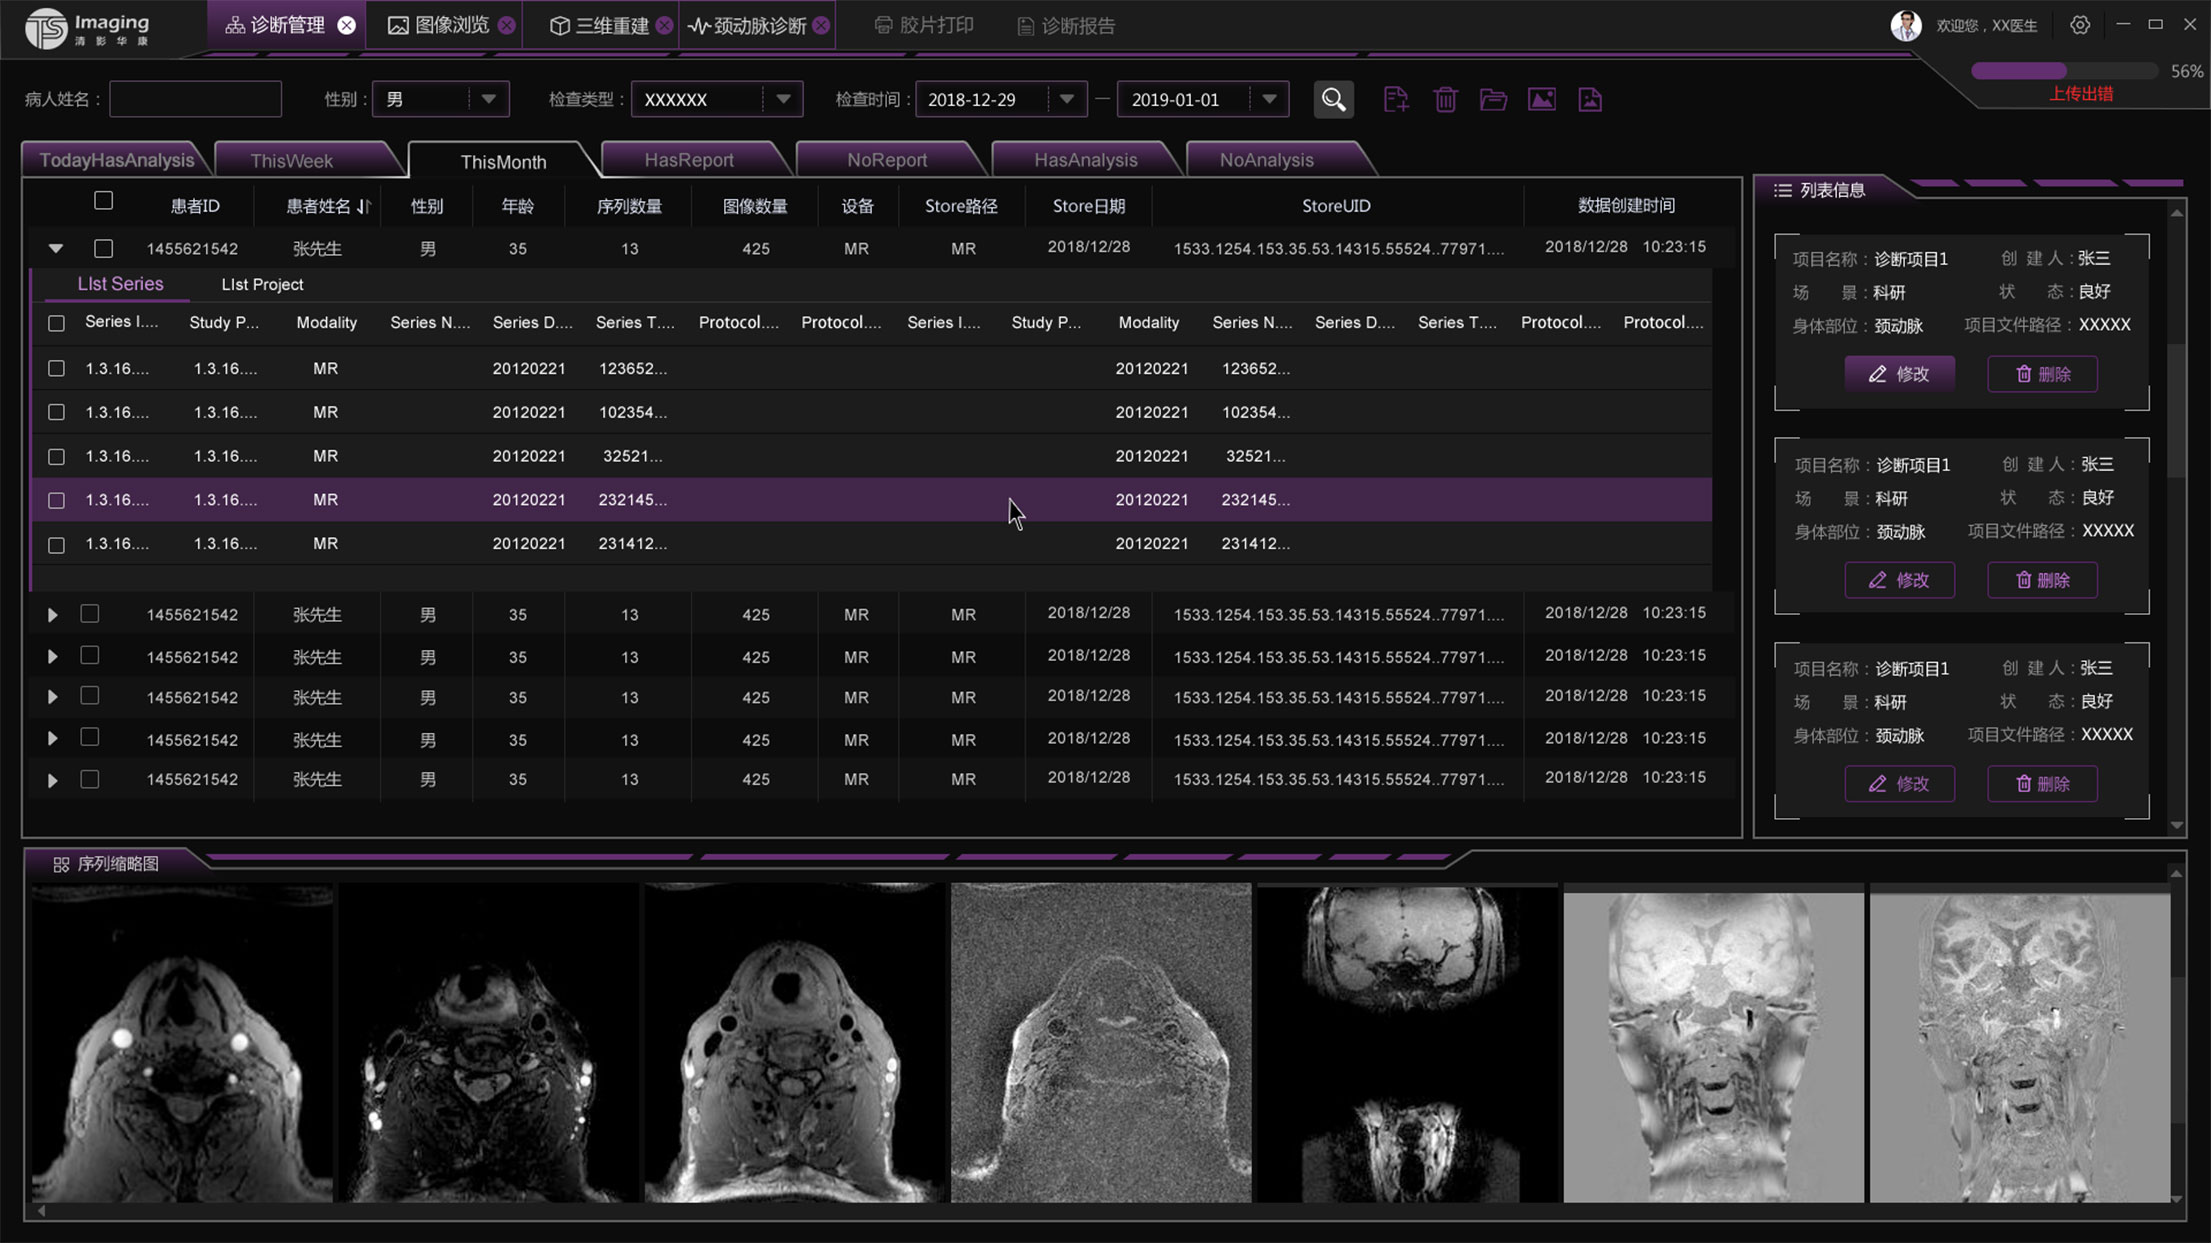

診斷管理頁面

診斷管理頁面相對其他頁來說交互關系比較復雜,表單里面還套了一個子表,為了更好的區分兩者,tab的形式、底色和字體大小等等做了明顯的區分。這部份也是在設計過程中調的較多的地方。左側是一個信息列表的展示,通過下方的按鈕也可進行操作。下方是影像的縮略圖,點擊之后可放大。